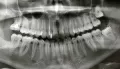

Вчера была у стоматолога, сделали снимок. Врач сказал, что пломбы на снимке хорошие, каналы запломбированы хорошо, ровно. Но, видит на кончике корня маленькое как будто воспаление. Сказал, что это может быть из-за простуды. Лечить не нужно, дал направление в физ.кабинет.